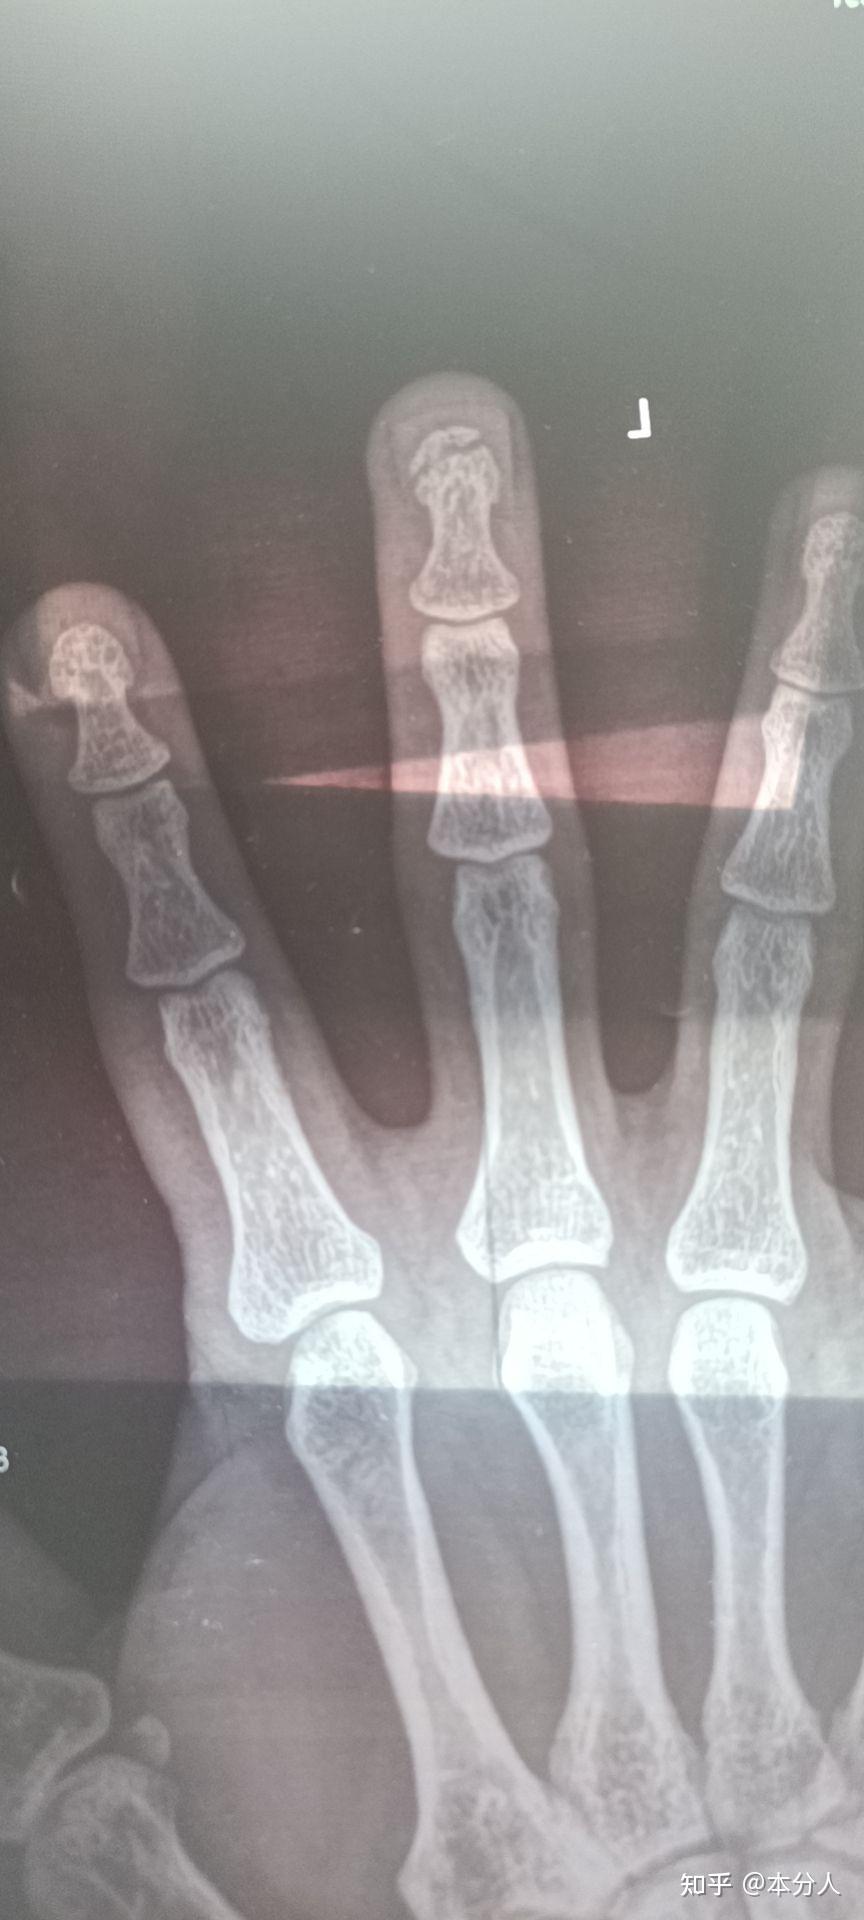

左手中指,环指指骨骨折闭合复位穿针内固定术